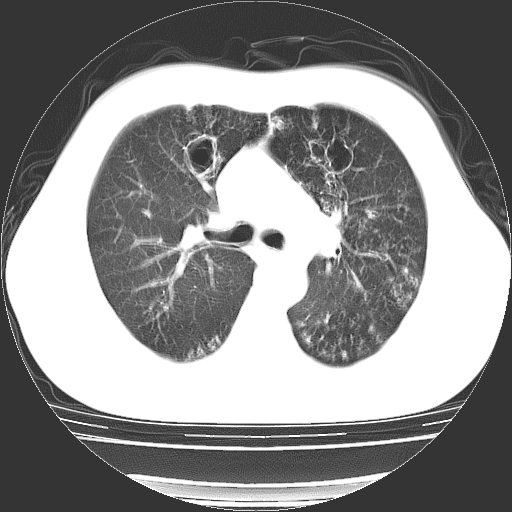

以下是引用zyx168在2006-12-4 15:30:00的发言:[br]经典!支气管肺囊肿并感染。

以下是引用dyqct在2006-12-4 17:11:00的发言:[br]典型的囊状支扩合并感染。

以下是引用liaoqiang在2006-12-4 16:12:00的发言:[br]局部肺叶内可见扩张的支气管壁,考虑为支扩。部份囊样影内有小液平和肺内散布斑片征影、小结节及纤维灶,提示支扩伴感染,且由于局部呈现有树芽征感染以结核可能性大。

以下是引用zhoucan076在2006-12-4 16:48:00的发言:[br]囊状支扩合并感染